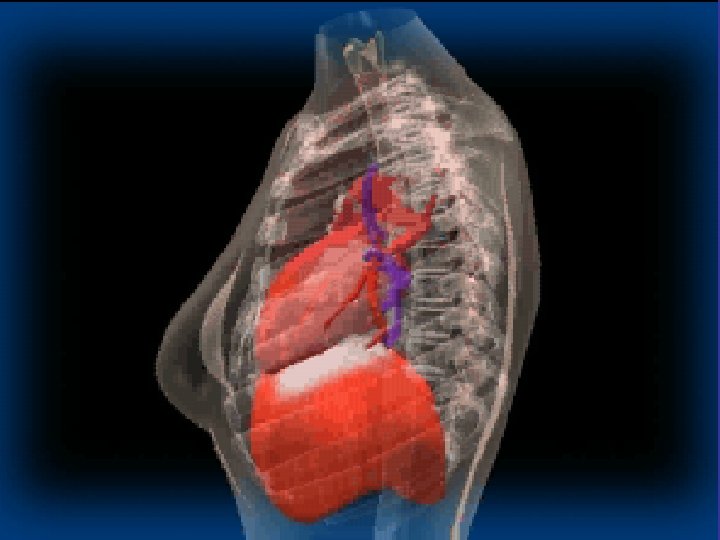

Lobes and Fissures